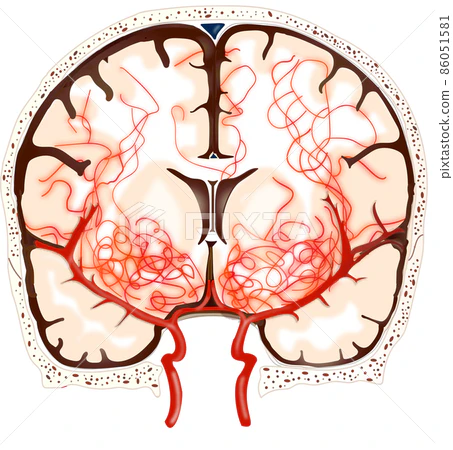

모야모야병(Moyamoya disease)은 특별한 원인 없이 뇌 속 특정 혈관, 주로 내경동맥 끝부분이 서서히 좁아지거나 막히는 만성 진행성 뇌혈관 질환입니다. 혈관이 좁아지면 뇌 혈류량이 감소하게 되고, 부족한 혈류량을 보충하기 위해 막힌 혈관 주변으로 가늘고 약한 비정상적인 미세혈관들이 자라나게 됩니다. 뇌혈관 조영술 이미지에서 이 미세혈관들이 마치 '연기가 모락모락 피어오르는 모양'과 같다고 하여 일본어로 '모야모야(もやもや)'라는 이름이 붙었습니다.

병태생리 측면에서 보면, 뇌혈관 협착에 대응하여 생성된 미세 혈관망이 특징적인 '연기 모양'을 나타냅니다. 최근 "기계-생물학적 이론(Mechano-biological theory)"은 혈관 구조의 차이 등 여러 요인이 복합적으로 작용하여 광범위한 뇌혈관 폐색을 유발하고, 손상된 뇌에 혈액을 공급하기 위한 혈관 연결의 변화를 초래한다고 설명합니다. 일단 발병하면 혈관 폐색은 알려진 내과적 치료에도 불구하고 계속 진행되는 경향이 있습니다.